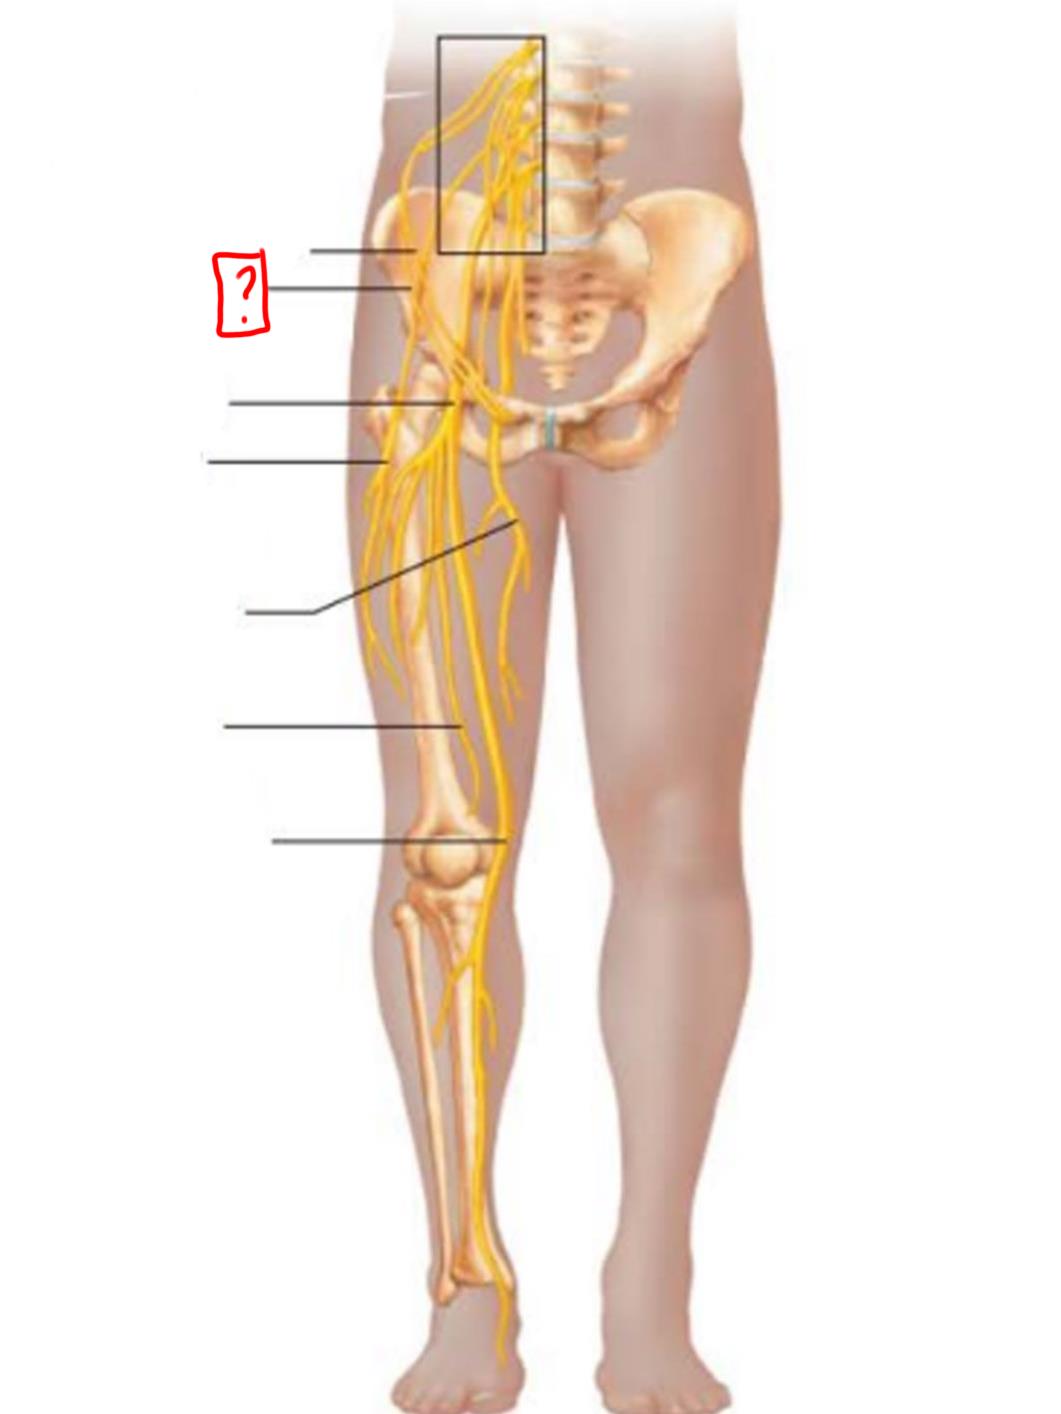

iliohypogastric

ilioinguinal

femoral

lateral femoral cutaneous

obturator

anterior femoral cutaneous

saphenous